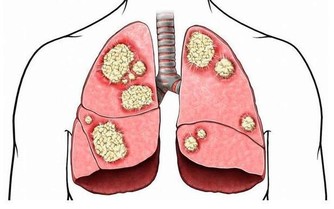

據流行病學的相關數據統計顯示,大約10%的高尿酸患者會發生痛風,痛風患者40%可繼發腎臟損害的表現!而且實際情況當中可比這個40%要高很多。

什麼意思呢?意思是雖然痛風一次次的發生,但是每次發生痛風都會對腎臟造成一定的損害!

但是醫學研究發現痛風產生的尿酸結石等病變早期主要影響腎小管的重吸收功能,使人體濃縮尿液的能力下降,這是在悄無聲息損傷痛風患者的腎臟,而且並不一定會反應為血肌酐升高。所以,在腎內科一般都認為痛風都會百分百引發腎臟損害!